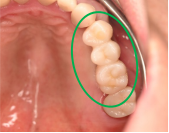

After

※緑丸は、今回埋入したインプラント

※黄色丸は、2006年10月に埋入したインプラント